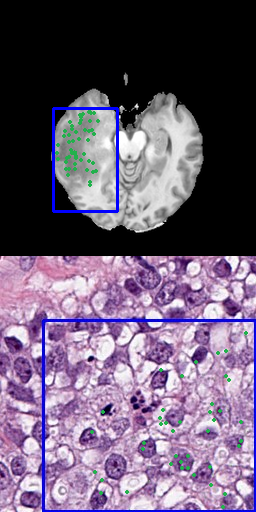

One approach is to use several positive points as input data that represent the goal label [8]. Using points as input is a precise method, allowing to preserve fine segmentation details but requires more annotation effort. When large areas are annotated, this is especially problematic. Figure 3 shows samples for using 3, 10, 50 or 100 points for the radiology and pathology data.

Refer to caption

(a) 3 positive points

(b) 10 positive points

(c) 50 positive points

(d) 100 positive points

Figure 3: Results for different number of positive points without bounding box

Table 3 shows the resulting segmentation performance when applying different numbers of sampling points with- and without bounding boxes. Figure 7 visualizes them as boxplots for the radiology dataset, while figure 8 shows the difference of the results in the given pathology dataset.

Both datasets show the trend that more points are consistently improving the segmentation performance. SAM can be trained on more sample points and can generalize better to more complex segmentation tasks. However, BCSS shows a significantly worsened performance with only three sampling points compared to BraTS as the fine segmentation at the cell level is more complex than in MRIs.

Consequently, with only three samples, the performance drops to a Dice of only 39.056% when using 3 points instead of 10 (Dice 79.697%). In the case of the radiology domain, this drop of the Dice is only from 66.818% to 61.879% due to the simpler features that can be robustly presented with few samples. Another interesting observation is that while in radiology adding a bounding box always improves the segmentation performance, this doesn’t help in the case of pathology and sometimes even decreases the performance. The large bounding box is unable to precisely represent the segmentation at the cell level. In radiology the segmentations are less fine and complex and therefore the bounding box helps to more extensively cover the segmentation which leads to a better model.

The only exception in the case of pathology is when adding a bounding box to the sampling configuration with only 3 points, which improves performance from the Dice of 39.056 to 77.802 as only three points don’t cover enough tumor area.

Overall, the results show that in radiology, even only a bounding box and/or three points are sufficient to achieve good performance. On the other hand, in pathology at least 10 points should be given as it significantly improves the results compared to only using 3 points or a bounding box. An alternative would be to use three points but combine it with a bounding box. These results show the potential to reduce workload in clinical applications as SAM is label efficient in both domains, with an advantage in radiology.